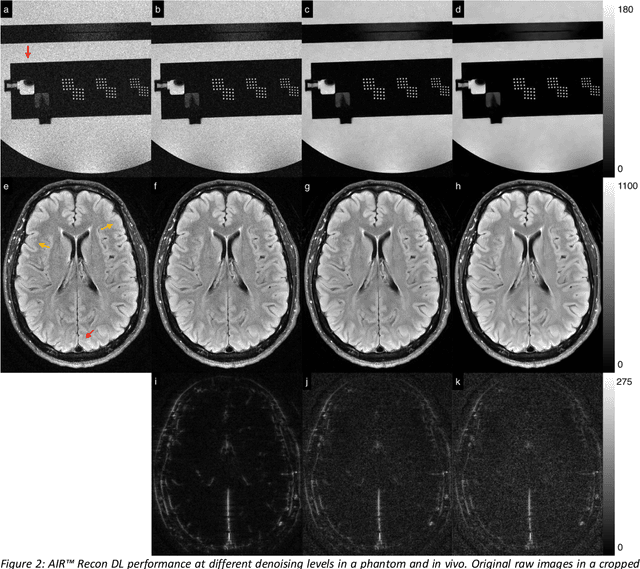

Abstract:A novel deep learning-based magnetic resonance imaging reconstruction pipeline was designed to address fundamental image quality limitations of conventional reconstruction to provide high-resolution, low-noise MR images. This pipeline's unique aims were to convert truncation artifact into improved image sharpness while jointly denoising images to improve image quality. This new approach, now commercially available at AIR Recon DL (GE Healthcare, Waukesha, WI), includes a deep convolutional neural network (CNN) to aid in the reconstruction of raw data, ultimately producing clean, sharp images. Here we describe key features of this pipeline and its CNN, characterize its performance in digital reference objects, phantoms, and in-vivo, and present sample images and protocol optimization strategies that leverage image quality improvement for reduced scan time. This new deep learning-based reconstruction pipeline represents a powerful new tool to increase the diagnostic and operational performance of an MRI scanner.